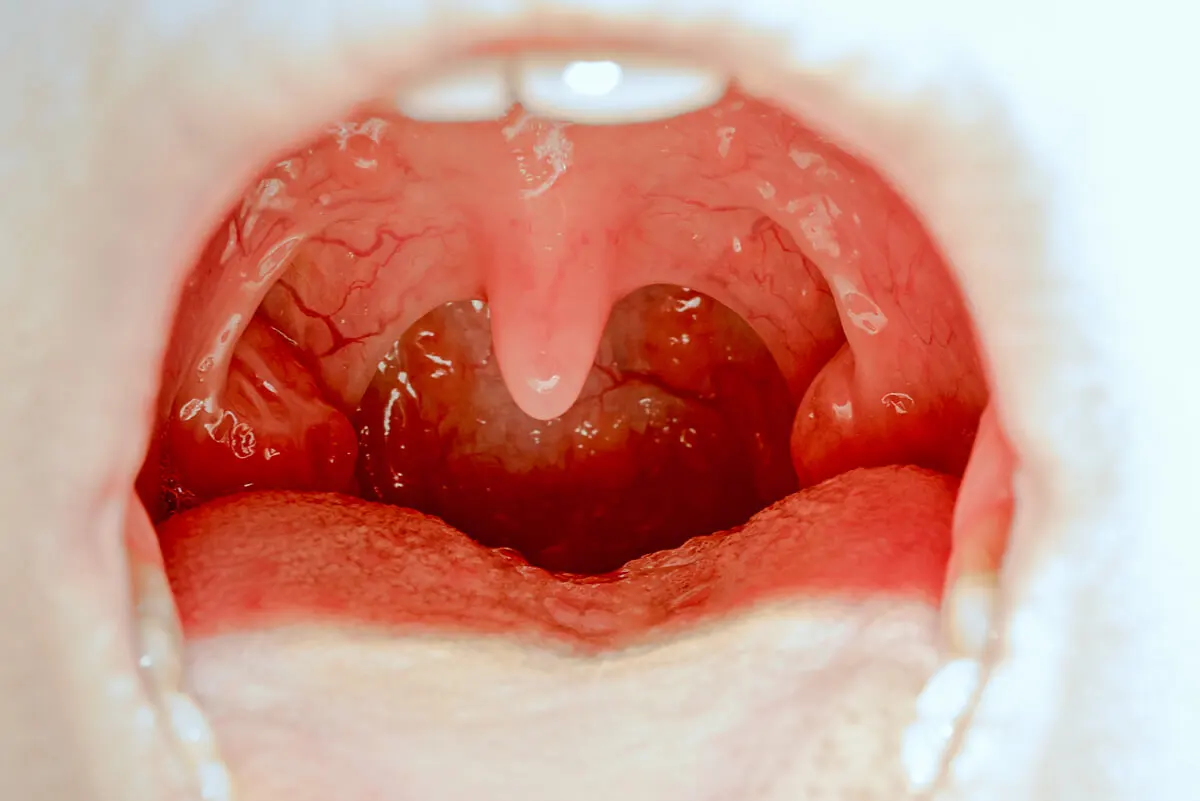

La amigdalitis vírica y la bacteriana no se diferencian mucho en sus síntomas. Es una enfermedad que cursa con fiebre, voz gangosa, dificultad para la deglución (disfagia) y dolor local. Según la Academia Americana de Otorrinolaringología, esta patología se define por una inflamación de las amígdalas palatinas o de la mucosa faríngea.

Todos estos porcentajes, en principio de naturaleza anecdótica, nos muestran la gran variedad de bacterias que pueden llegar a generar un cuadro de amigdalitis bacteriana en infantes. Esta forma se considera más severa que la variante vírica, pues se desarrolla con fiebre elevada, dolor intenso de garganta y la aparición de placas de pus y mal aliento.